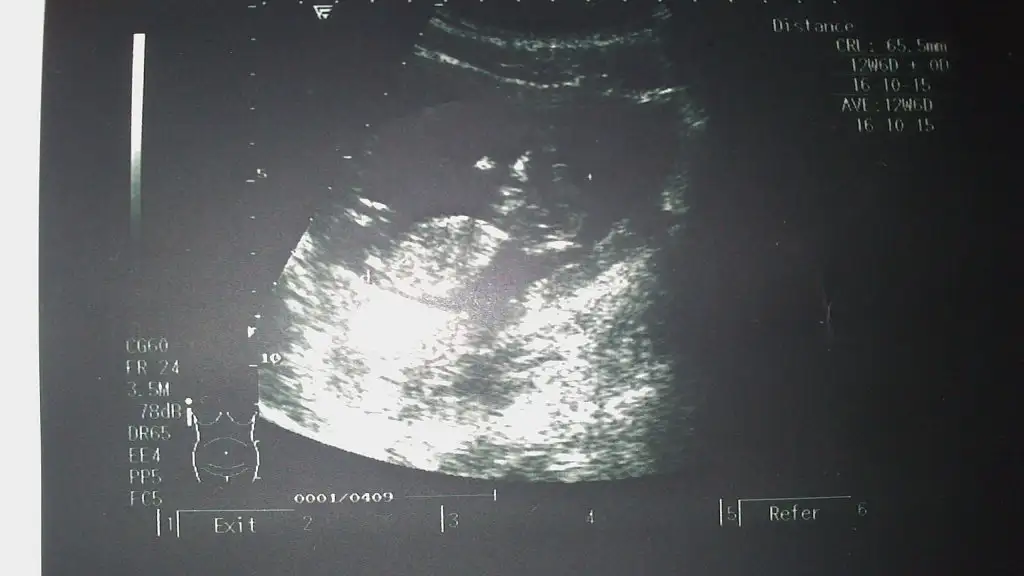

dr soylemeden siz gorun genital nub teorisi ( bebegin cinsiyeti)

Kizlar resmimi ekliyorum tahminlerinizi bekliyorum.simdiden yorum yapanlara tesekkurler :KK39::KK68:

Eklentiler

• IMG-20150409-WA0003.webp

IMG-20150409-WA0003.webp

16,4 KB · Görüntüleme: 105